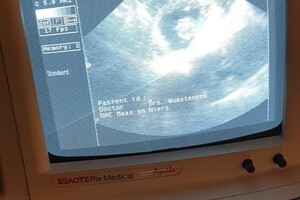

de dierenarts mocht Dakota eerst scheren, dit had ze nog niet eerder meegemaakt, maar ze vondt het niet zo erg, daarna heeft de dierenarts de scan gemaakt:

Ze is drachtig. het blijft moeilijk te zien hoeveel puppy's we kunnen verwachten, maar de dierenarts gaf aan dat we een mooi nest krijgen: niet te groot en niet te klein nest, ze ging uit van 4 a 5 puppy's. Dierenarts verwacht dan ook geen complicaties en een natuurlijke bevalling.